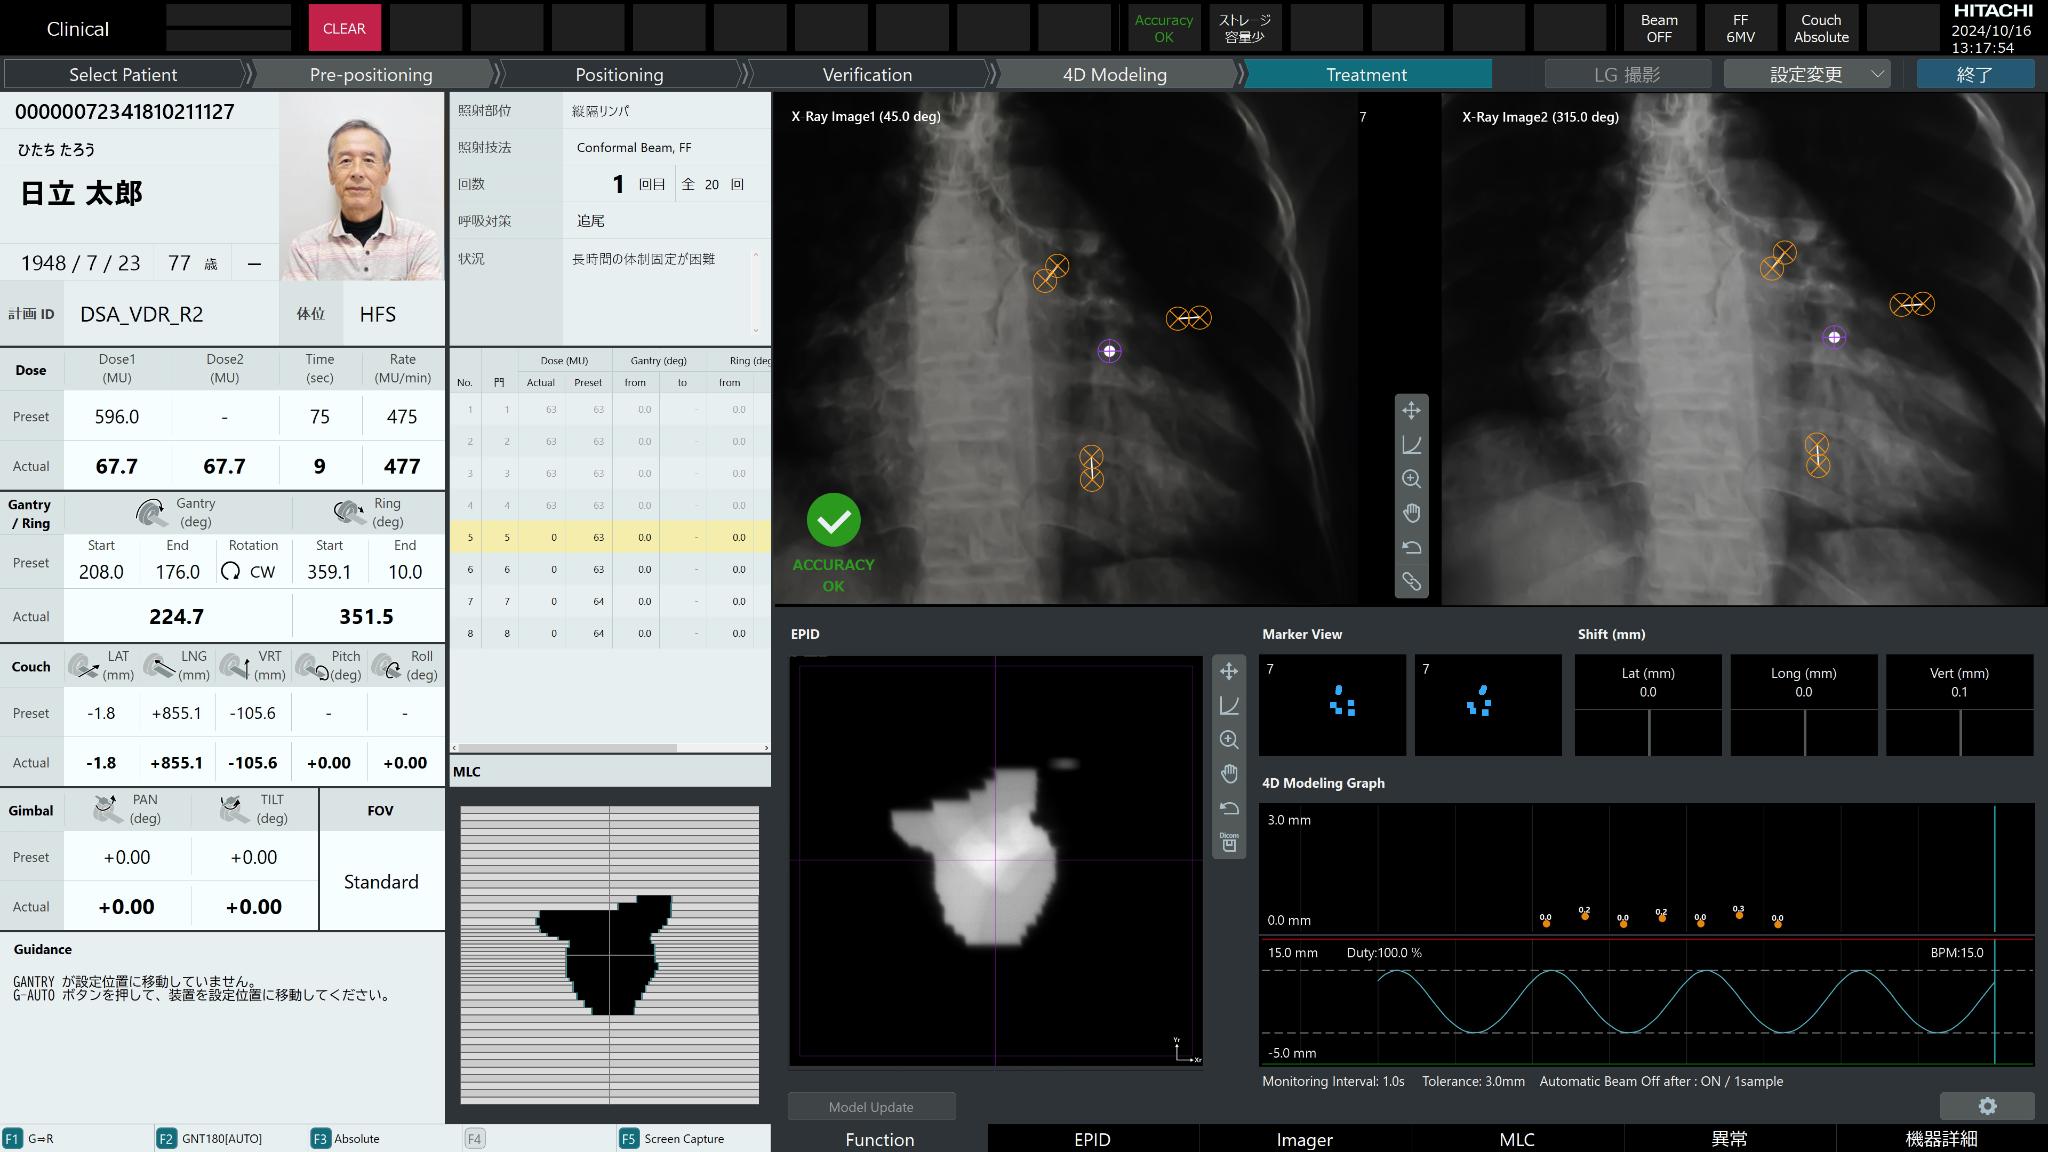

Hitachi High-Tech, Ltd.The OXRAY is a cancer treatment system in which the stage and the inside of the gantry rotate on two axes to deliver X-rays from various angles. The gimbal function enables dynamic tracking of cancer tissue that moves with respiration, which reduces the physical burden and enables high-precision treatment. This reduces side effects and treatment time. In addition, the irradiation range has been expanded to accommodate more cases, and throughput has been significantly improved by integrating individual systems. As of 2025, the system will be available only in Japan.